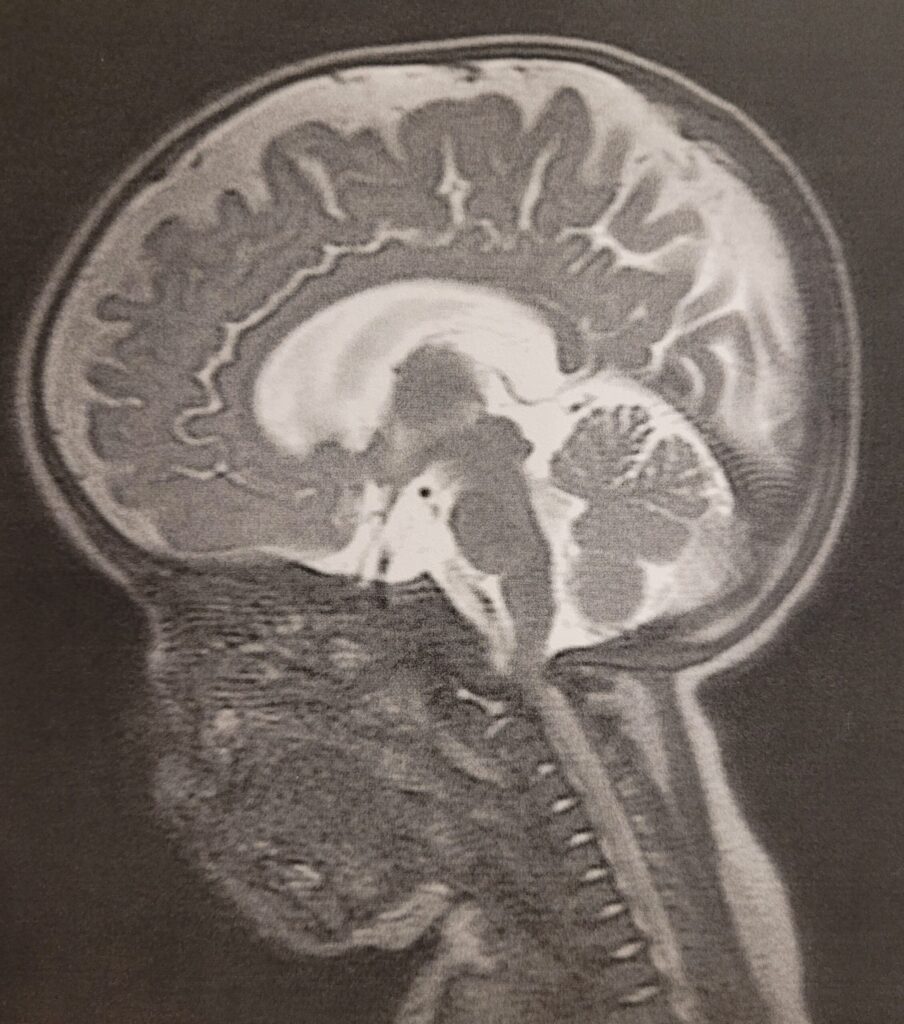

こちらが最初に撮ったMRI画像とその後全身麻酔で撮ったMRI画像です。このブレブレの画像で手術に踏み切ろうとしたなんて…今考えただけでもゾッとします…

※この時は脳神経外科手術が必要かどうかの診断をするため、頭蓋骨ずがいこつ・とうがいこつのMRI撮影をしました。

・セカンドオピニオンでのMRI撮影